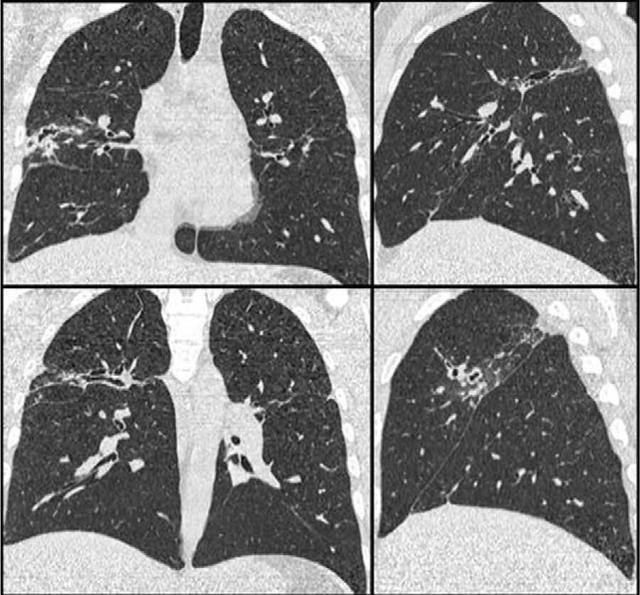

這位廣西患者幸虧發現得早,不然時間拖久了可能會引發嚴重的後果。因為肝吸蟲在晉陞的過程中會產生毒素和一些分泌物,損傷肝細胞和膽管上皮細胞。肝吸蟲寄生以後引起的病變,包括膽管阻塞、膽汁性肝硬化、膽結石以及膽上皮的異常增生。

此外還可引起侏儒症,就是肝吸蟲寄生在肝膽管內,會導致管腔狹窄,管壁增厚。感染肝吸蟲以後,輕度感染無明顯的臨床癥狀,重度感染者可出現上腹部不適、疲乏、食慾不佳、厭油、消化不良以及腹瀉、肝區隱痛等癥狀。

巨片型吸蟲最大的可以達到四五公分,四五公分的蟲子放在你的肝臟里,吃你的肝臟,想想就疼。但嚴格意義上講,這種寄生蟲並不是把人類的肝臟吃掉了,而是對人類的肝臟進行啃噬,導致肝臟出現一些空隙,長時間下去會造成壞死,最後這些組織就會溶解,消失不見。